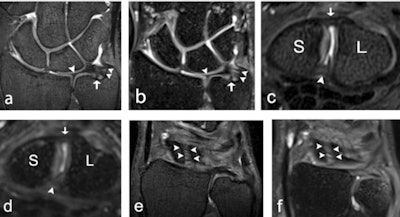

Because improved visualization using noninvasive methods could be of clinical value, a team from Lund University aimed to evaluate visualization of structures at 7-tesla compared with 3-tesla MRI using a dedicated, commercially available wrist coil.

"At our institute, hand surgeons and radiologists wanted to investigate whether the higher field strength could improve visualization of wrist ligaments, as current diagnostic imaging often is unsatisfactory when wrist ligament injury is suspected," Dr. Simon Götestrand, lead author and radiologist at Lund University Hospital, told AuntMinnieEurope.com.

Robust results

The team graded all evaluated anatomical structures, including ligaments, trabecular bone, cartilage, nerves, and tendons, as better visualized at 7 tesla compared with 3 tesla, with an area under the curve (AUCVGC) of 0.62-0.88 (95% confidence interval [CI] 0.50-0.97, p = < 0.0001-0.03) using either 2D or 3D imaging. Specifically, 7 tesla was significantly superior to 3 tesla in the evaluation of edge sharpness and perceived tissue contrast. There was no significant difference in grading regarding artifacts. Importantly the results also revealed that MRI of the wrist at 7 tesla with a commercially available wrist coil is feasible at similar acquisition times as for 3 tesla MRI.

Limitations of the current study were the small number of subjects and the lack of pathology in the study population. Also, the 3D sequences were optimized for ligament visualization, which may have resulted in a less optimal visualization of other structures. However, the authors underlined that the study demonstrated overall, that wrist structures are better visualized at 7 tesla compared with 3 tesla, this better visibility and delineation likely to translate into better detection and definition of pathology.